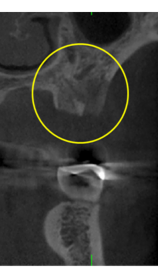

抜歯のう胞摘出

Perio Wave+Er:YAGレーザー+コールドレーザーで治療した箇所の経過です。

左から直後、1ヶ月経過時、2ヶ月経過時の画像です。

骨再生の確認をした際の動画です。

画像をクリックすると、youtubeにジャンプします。